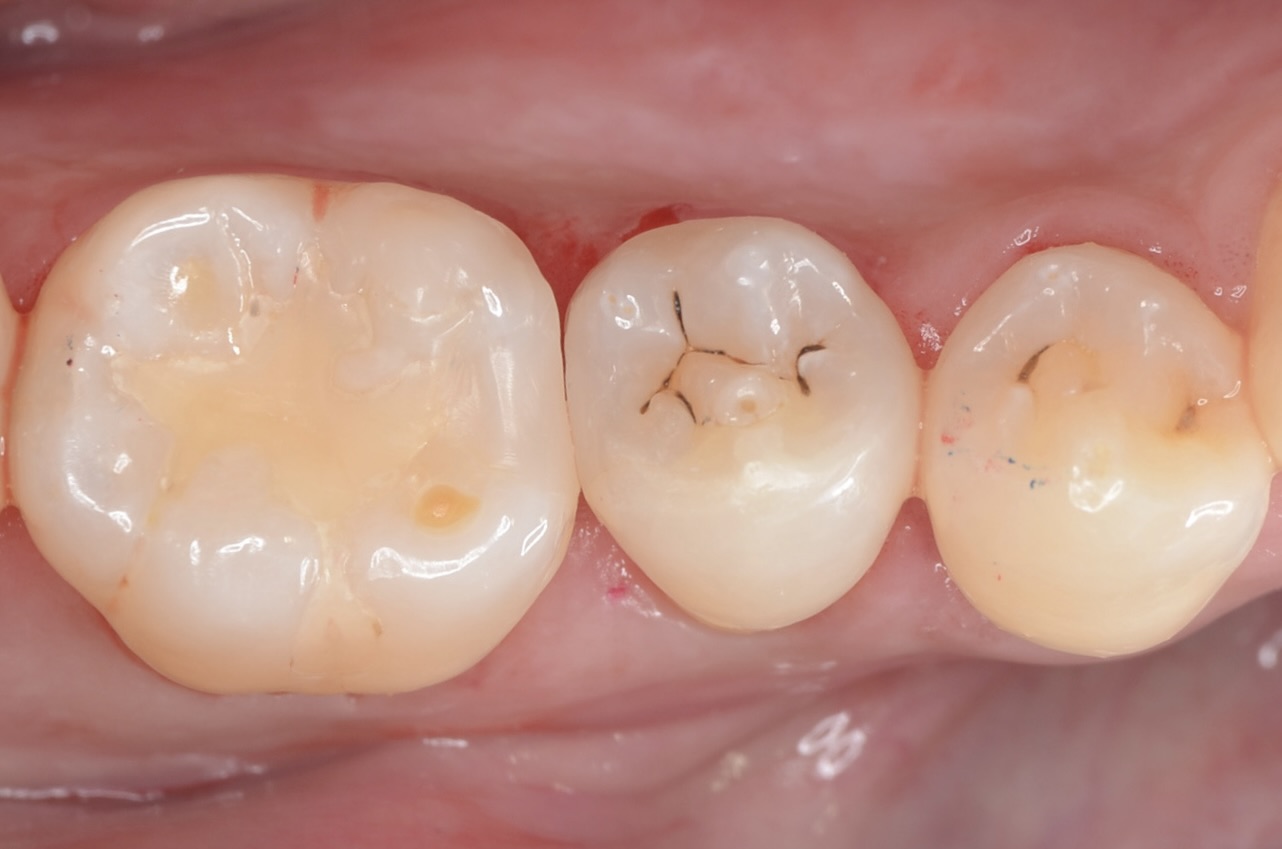

Before

6番側方面観

歯と歯茎の境に古いレジン充填があります。その縁が黒ずみ虫歯になっています。 -